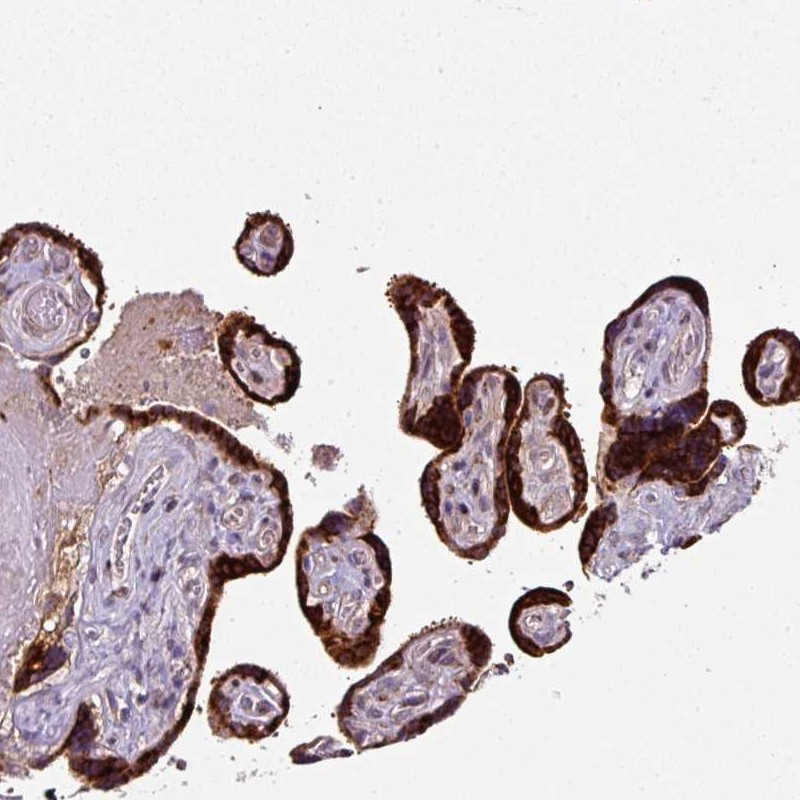

Immunohistochemical staining of human placenta shows strong cytoplasmic positivity in trophoblastic cells.